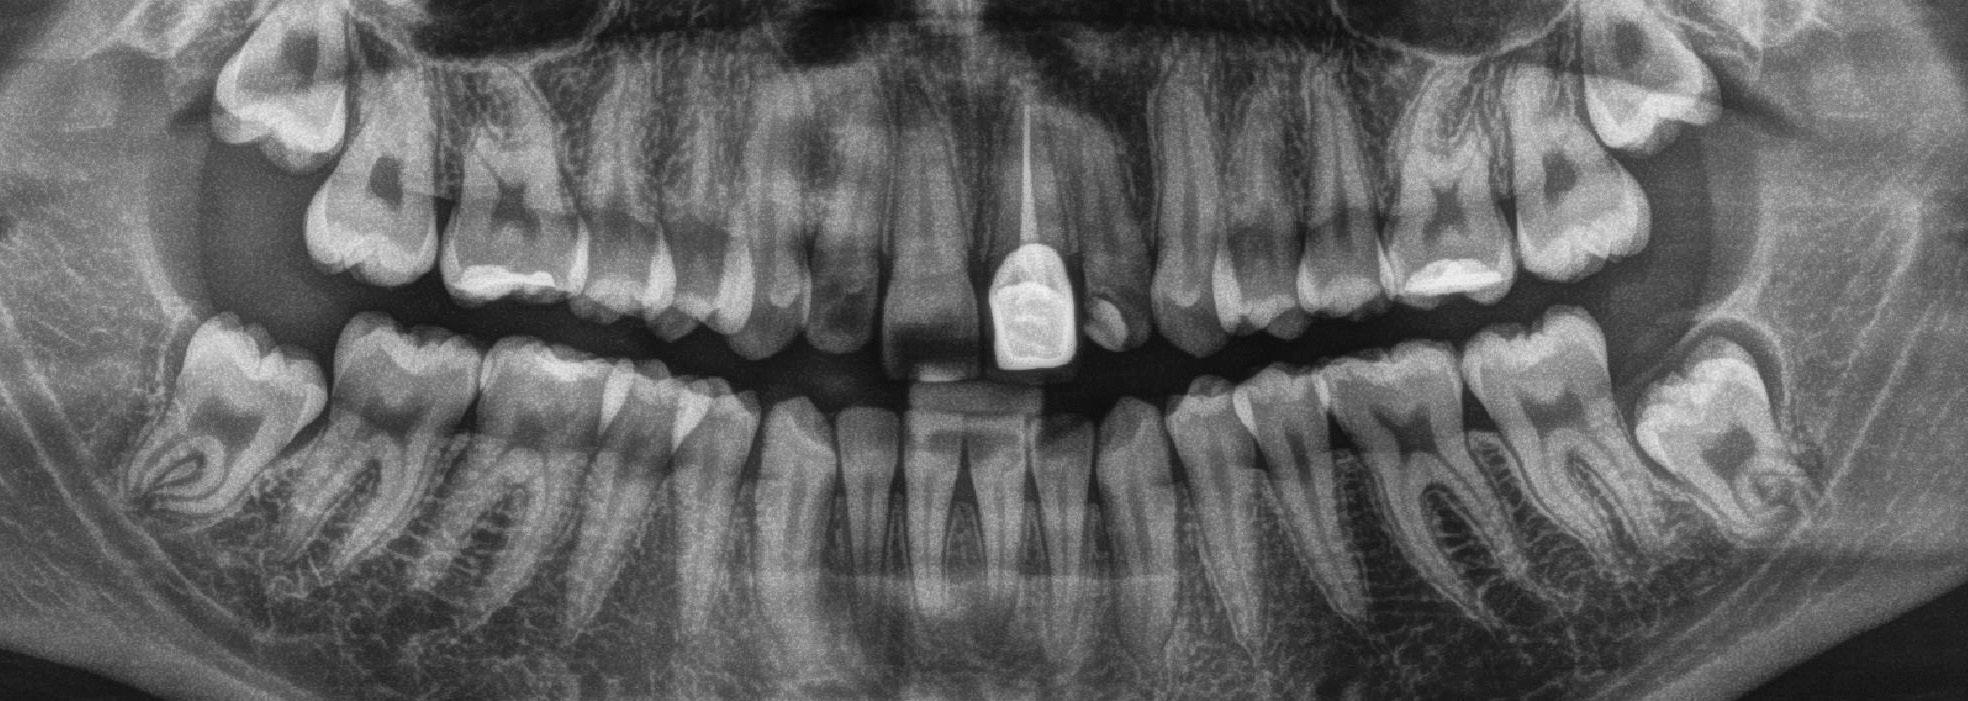

protection from needle stick injuries

security

for the patient

Transparent